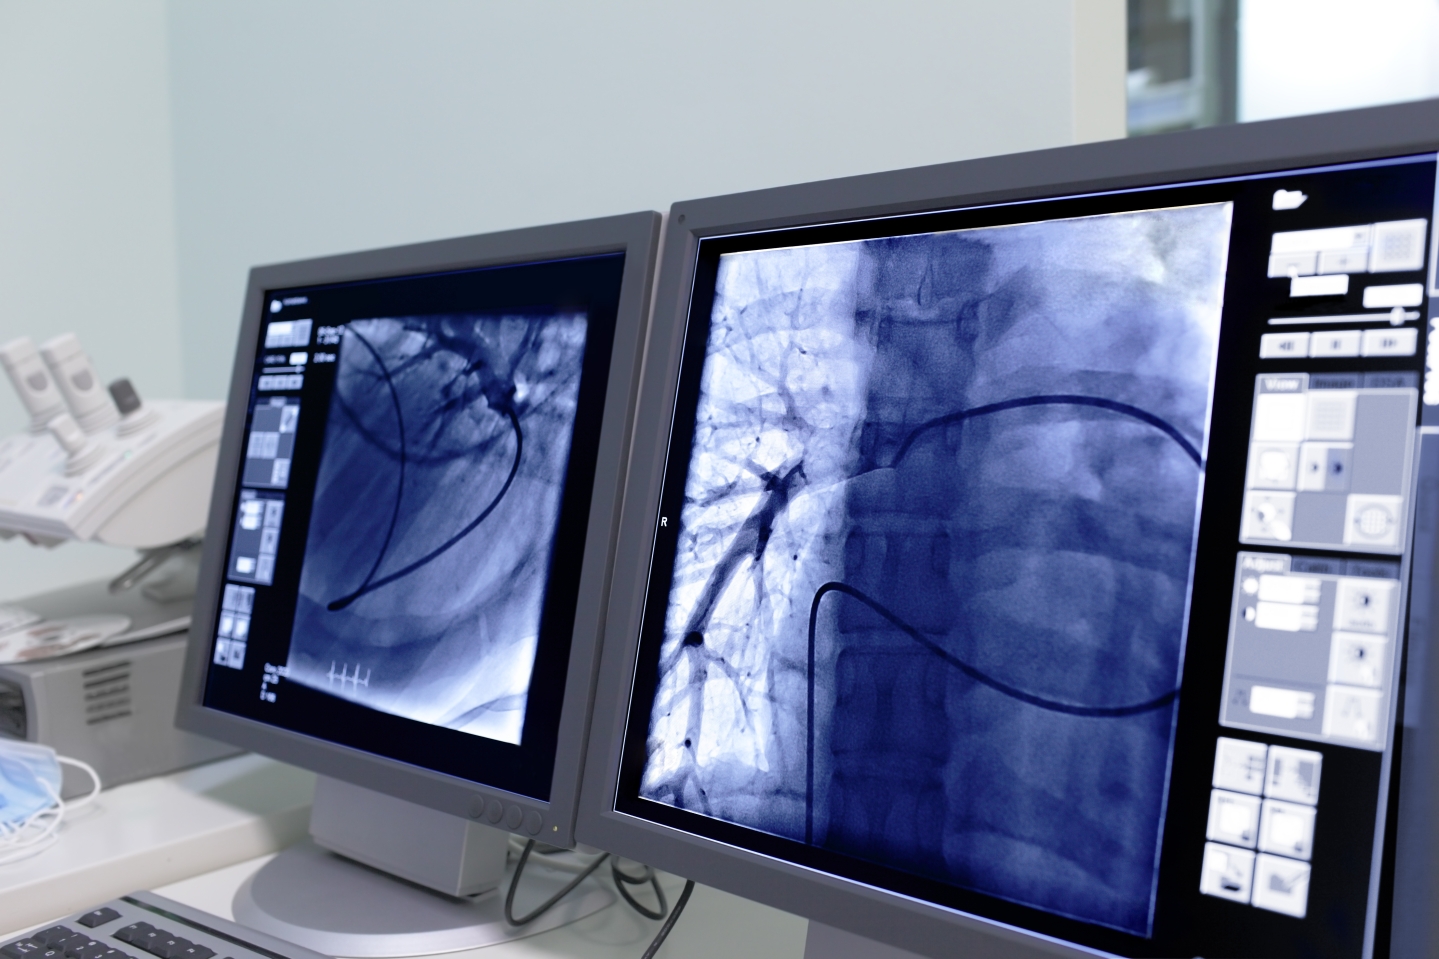

Bei der Embolisation wird über einen Katheter verschließendes Material direkt an die benötigte Stelle im Gefäß eingebracht. Zum Einsatz kommen je nach individueller Situation Medikamente, hochkonzentrierter Alkohol, Gefäßkleber, Kunststoffkügelchen oder Metall. Der minimalinvasive Eingriff ist röntgen-, CT- oder MRT-überwacht und muss äußerst präzise erfolgen. Deshalb wird die Embolisation nur von spezialisierten Radiolog:innen durchgeführt. Bei Evidia steht ein Team aus Expert:innen für die ganze Bandbreite dieser Therapieform zur Verfügung, ebenso wie moderne radiologische Geräte.

Einen besonderen Schwerpunkt der Embolisation bildet, neben der Therapie von Tumoren und Fehlbildungen, die Behandlung von zerebralen Aneurysmen. Erfolgreich ist hierbei häufig das sogenannte Coiling, sprich: das Einsetzen einer Mikrospirale aus Platin. Der Coil wird an die richtige Stelle im Gefäß gesetzt, wo er sich nach der Platzierung aufwindet. Um die Coil-Maschen bildet sich dann eine Thrombose, die das Aneurysma wirksam verschließt.